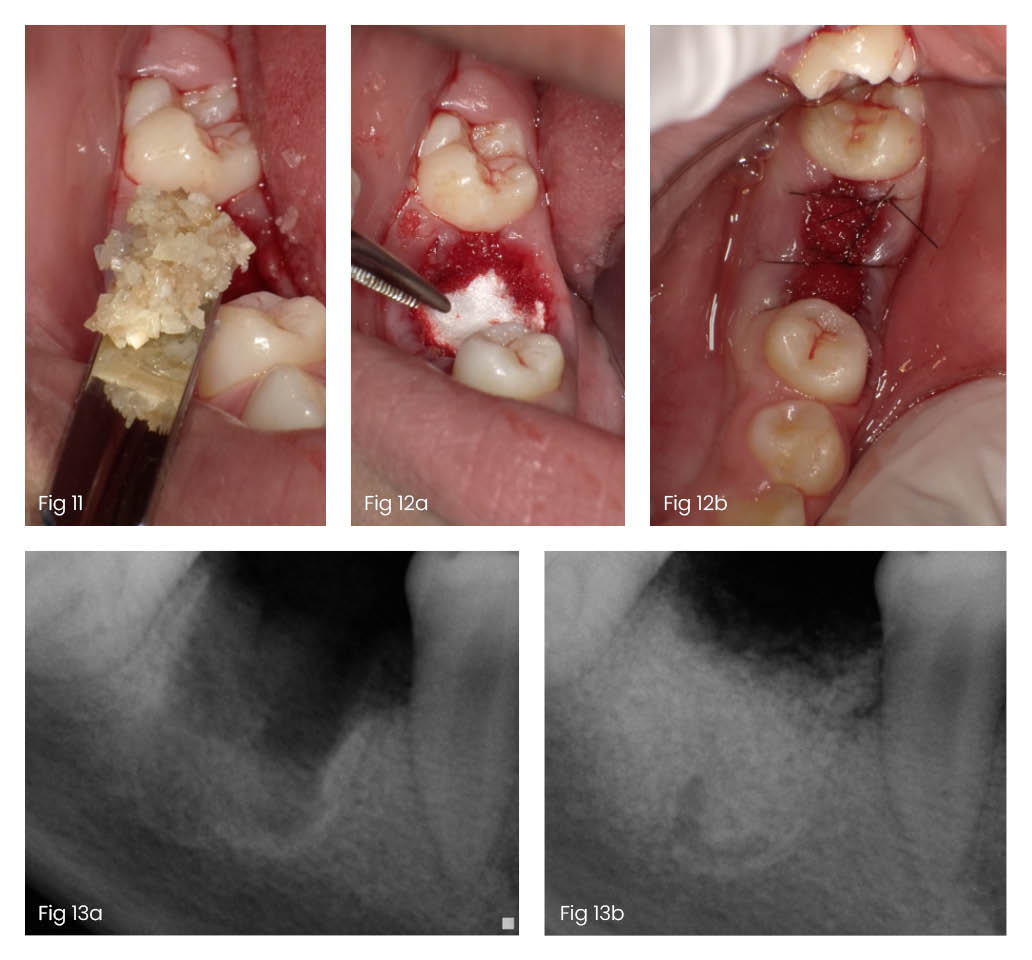

To your surprise, the dentist tells you that the tooth won't be discarded-it will be ground into tiny particles, sterilized, and placed back into the extraction site to help the wound heal faster and better, the process which is better known as Autogenous Dentin Graft. This unexpected twist turns an ordinary extraction into an innovative healing process, where your tooth contributes to your recovery in a way you never imagined. Contrary to that if you skip the plan and throw the teeth away, your ridge shrinks, by a process known as Residual Ridge Resorption.

Your dental practitioner transforms your extracted tooth into Autogenous Dentin Graft - a natural, effective way to speed up healing and restore your jawbone.